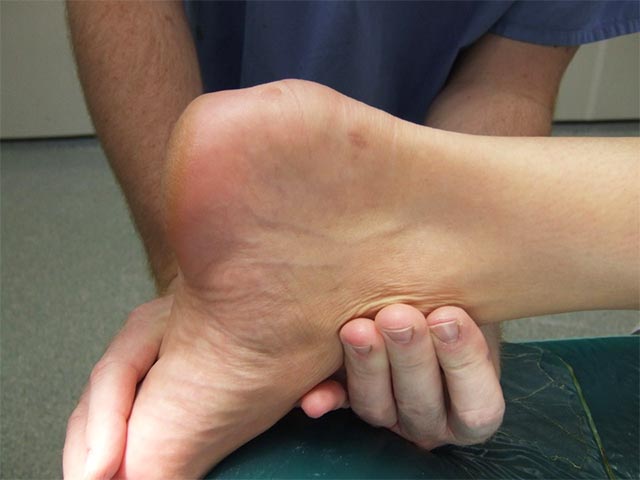

這位病人是一名護士,工作涉及很多站立,走動或搬抬病人的動作;而本身熱愛運動,尤其是行山。逐漸發覺後腳跟位置出現疼痛及凸出的增生物。每當站立及行走長時間,後腳便會發炎疼痛,嚴重時更會影響行路。嘗試服用消炎止痛藥及物理治療都未見改善,對日常生活及工作造成極大困擾。

病人最終在X光檢查下,發現後腳跟位置先天骨頭增生突出,症狀學名為。由於先天骨頭形狀;再加上後天因素,長時間跳躍、行路、站立等動作,漸漸後腳跟骨增生與阿基里斯跟腱形成重覆磨擦,因而誘發腫脹發炎。